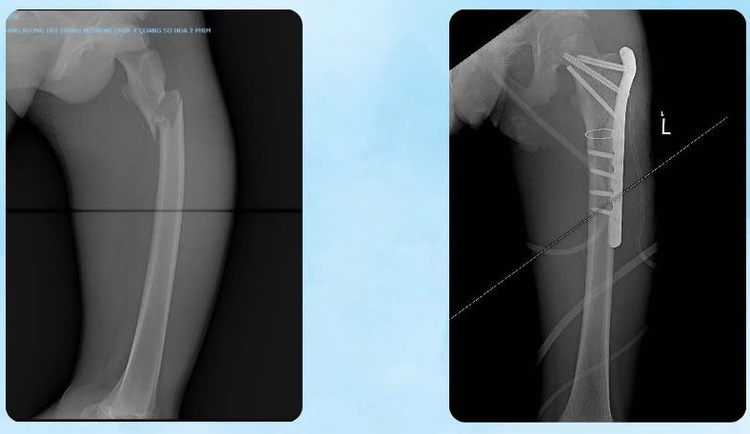

Kết quả chẩn đoán cho thấy bệnh nhân bị tổn thương nặng ở nhiều cơ quan: Chấn thương ổ bụng, gãy thân xương đùi, tổn thương phần mềm vùng bụng lưng chậu, chấn thương lồng ngực và thận. Đặc biệt, bệnh nhân bị gãy trật cột sống nặng tại đoạn L2–L3, kèm máu tụ ngoài màng tủy, tủy dập và rách màng tủy - tình trạng có nguy cơ để lại di chứng rất nặng.

Hình ảnh gãy trật cột sống nặng đã được nắn chỉnh - Ảnh BVCC

Khoa Ngoại Thần kinh: Tiến hành phẫu thuật vào cột sống lối sau, nắn trật cột sống đoạn L2–L3 và làm vững toàn bộ đoạn cột sống bị tổn thương bằng nẹp vít cuống cung dưới hướng dẫn C-arm; Đồng thời cắt bản sống L2–L3, lấy máu tụ ngoài màng tủy giải phóng chèn ép tủy, xử lý vùng tủy dập và vá màng tủy bị tổn thương.